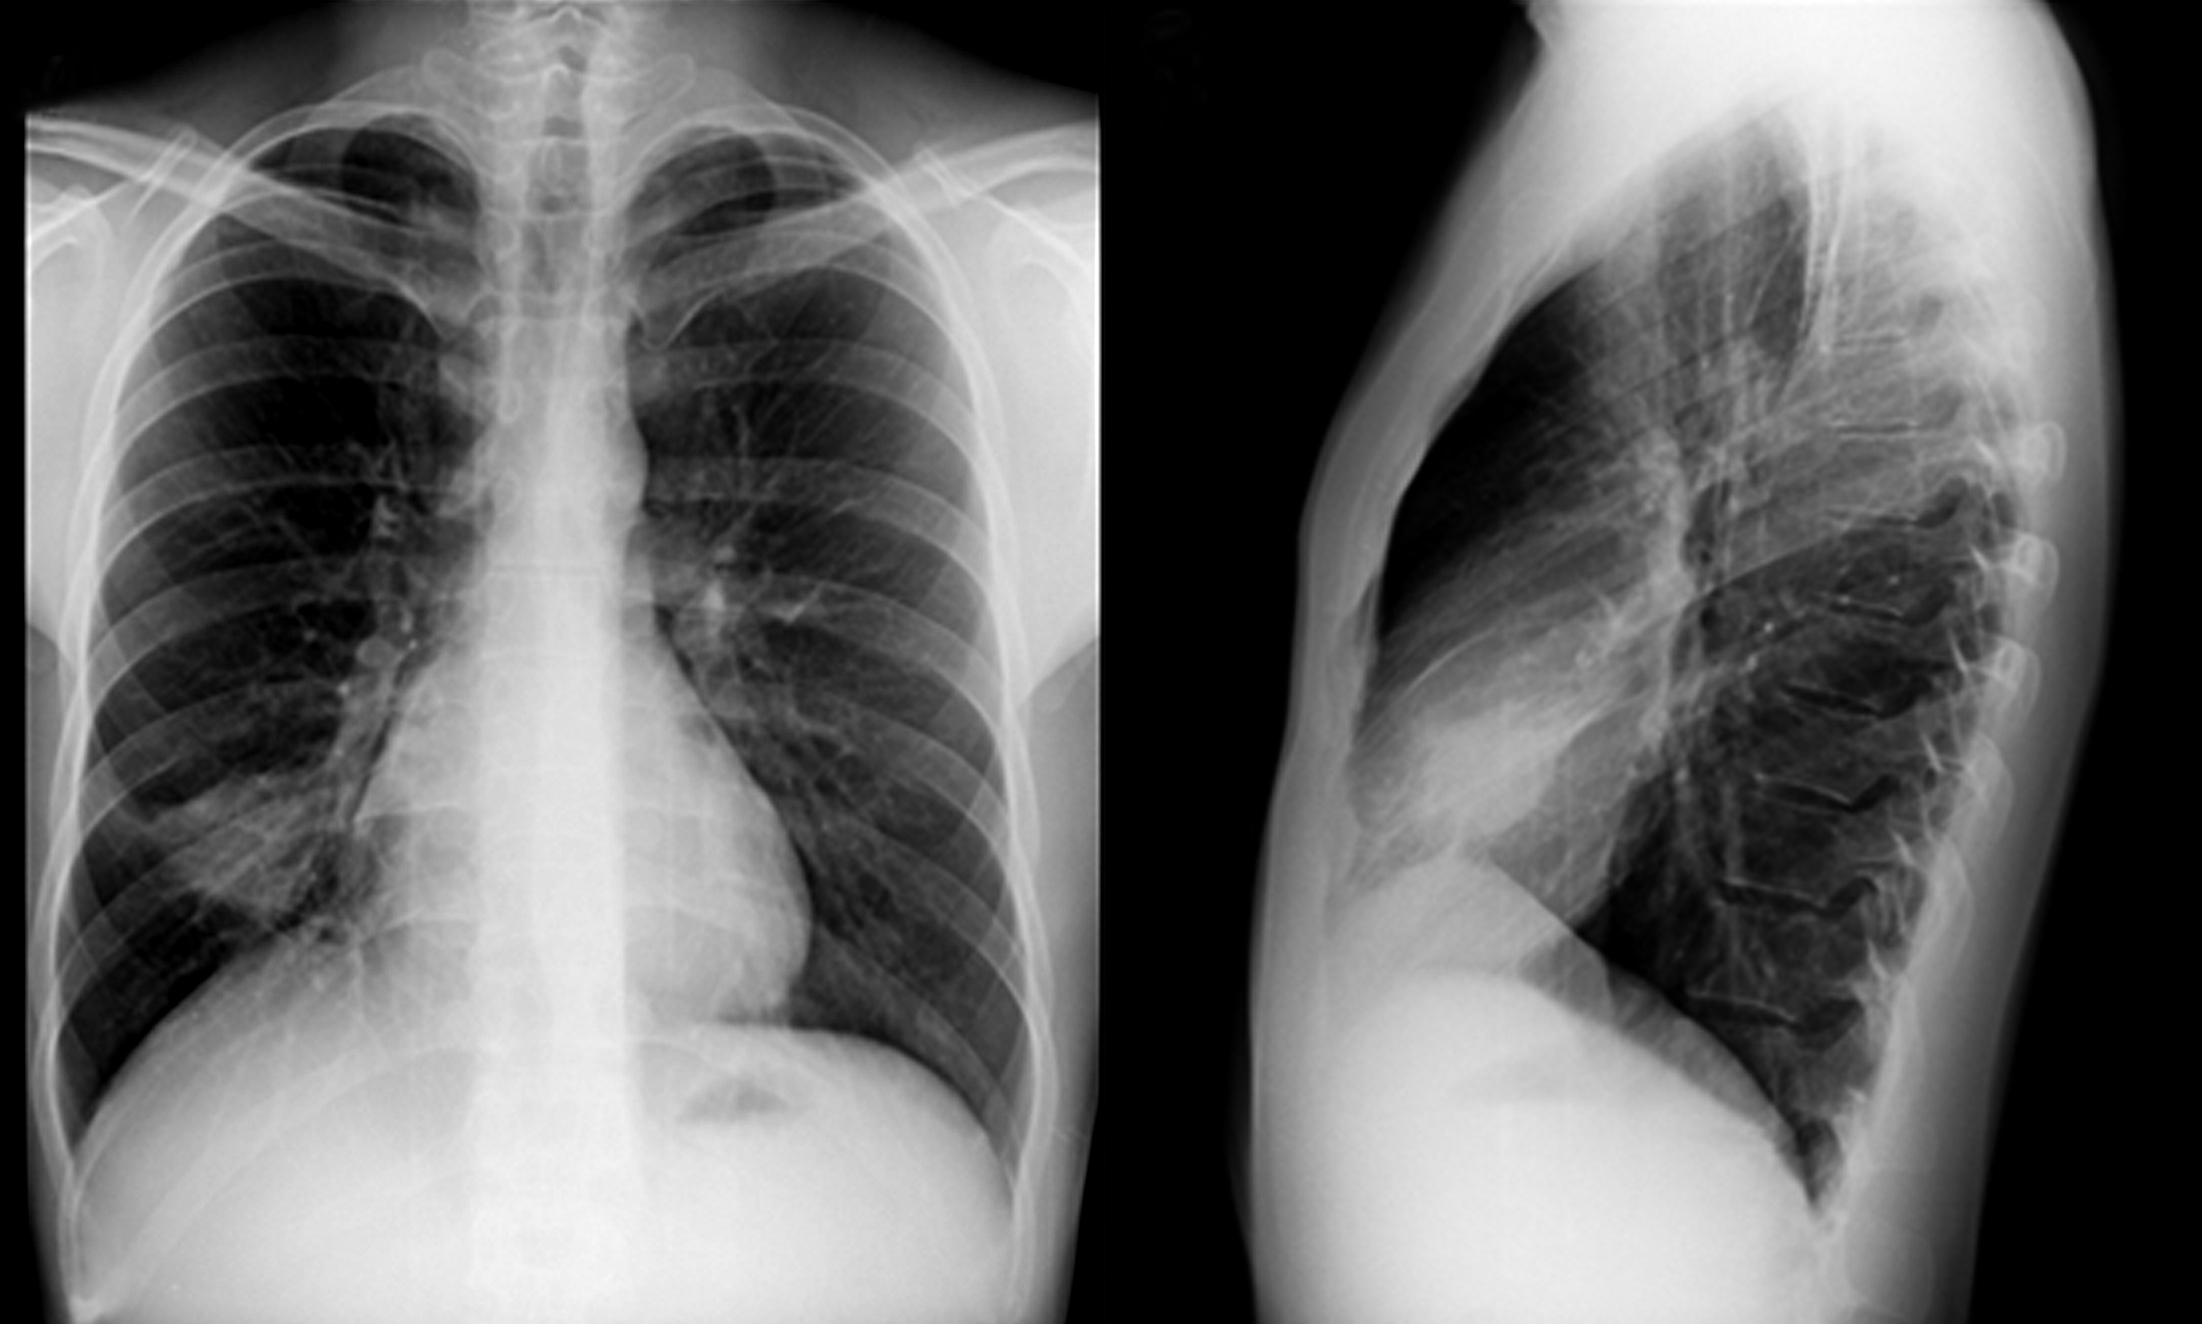

Se solicita radiografía de tórax de frente, en la cual se observa masa en tercio inferior de hemitórax izquierdo, retrocardíaca, redondeada, de bordes bien definidos, de aproximadamente 4 cm de diámetro. Resto del parénquima pulmonar y silueta cardiomediastínica sin alteraciones. (Figura 1)

Figura 1

Radiografía de tórax, proyección PA (a) y aumento del sector de interés (b). Se observa masa retrocardíaca en hemitórax izquierdo (flecha).

Se solicita radiografía de tórax de frente y perfil (Figura 4) en la que se observa una masa localizada en lóbulo medio, redondeada, bien delimitada, de 4 cm de diámetro mayor, sin otras alteraciones en campos pulmonares y silueta cardiomediastínica.

Figura 4

Radiografía de tórax, proyección PA (a) y perfil (b) donde se observa masa redondeada bien definida situada en el lóbulo medio.